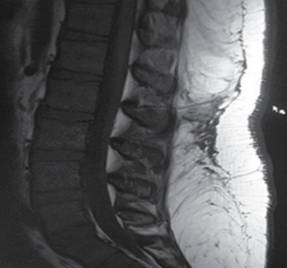

Se realiza resonancia magnética de columna lumbar, observando la presencia del catéter en el espacio epidural y se decide el retiro quirúrgico, explorando el canal medular (Figura 1).

Figura 1: Resonancia magnética, corte sagital, donde se demuestra la presencia de catéter epidural después de intento de retiro.